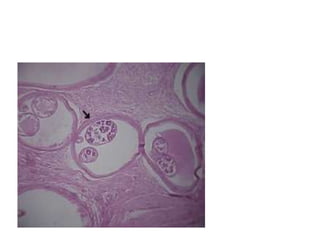

Photomicrograph showing adult worm cut in several planes with many

microfilariae also seen separately within the necrotic tissue. Surrounding

tissue shows dense inflammatory cell infiltrate consisting of polymorphs,

lymphocytes, eosinophils, foamy histiocytes, and small multinucleated giant

cells (H and E, ×200)

Photomicrograph showing sections of adult filarial

worms containing numerous microfilariae